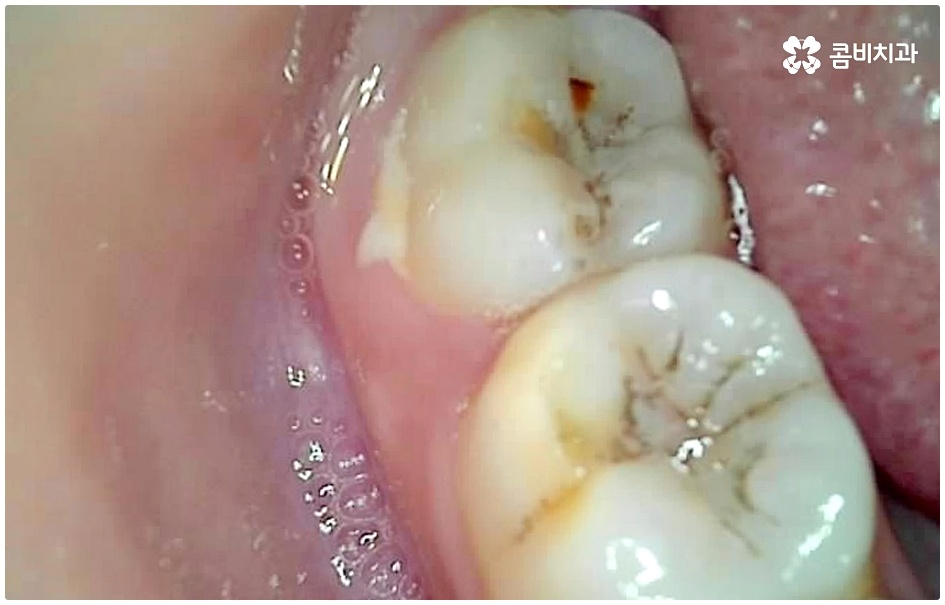

식습관보다 중요한 것은 이후 관리라고 할 수 있는데요. 칫솔질을 할 때 치실을 사용하여 치아 사이사이 부산물이 남지 않도록 꼼꼼하게 제거해 주시는 것이 필요하고 외부에서 식사 후 또는 커피나 간식 등을 먹은 다음에 양치질을 바로 하기가 어려운 상황이라면 음식물 찌꺼기가 잔류하지 않고 입 속이 산성화되는 것을 방지하기 위해 물로 충분히 헹궈주는 것이 도움이 될 거예요.

이 때 교합면, 즉 치아의 씹는 면이 아닌 치아 사이 충치가 생겼다면 쉽게 발견하기도 어렵고 치료를 위한 접근 역시 까다롭기 때문에 주의하실 필요가 있습니다. 물론 가장 흔하게 발생하는 것은 넓고 홈이 파여 있으며 직접 음식물을 저작하는 교합면에 생기는 충치일 것이나 음식물 찌꺼기가 끼기 쉽고 세균이 서식하기도 쉬우며 양치질을 하더라도 칫솔모가 잘 닿지 않기 때문에 관리가 어려운 치아 사이 좁은 틈새에도 역시 충치가 잘 생길 수 있는 거예요.

인접면 충치는 일반적으로 양치를 꼼꼼히 하기 어려운 아동에게 많이 발생하지만, 식습관이나 구강위생 관리 소홀 등을 이유로 성인에게도 빈번히 발생하는 질환이며 발견과 치료에 있어 일반적인 충치보다 어려움이 크기 때문에 주기적인 명동치과 검진 및 스케일링 처치, 그리고 치실 사용 등 꼼꼼한 양치질 등을 통해 초기 대처 및 예방을 해주는 것이 매우 중요하다고 할 수 있습니다.